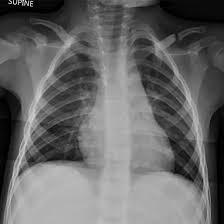

Medifyhome has collaborated with the best pathology laboratories that are NABL and NABH certified and follow ISO safety guidelines to provide the best NCCT for Clavicular Joint at an affordable price for needy individuals. NCCT over the clavicular joint is a recent imaging modality used to create cross-sectional images regarding the clavicle with less complexity without contrast. This minimally invasive process uses the highest quality X-rays that are a crucial diagnostic aid when it comes to different ailments associated with the shoulder and collarbone regions. Thus, NCCT is especially efficient in the examination of fractures, dislocations, tumours, infective processes, and degenerative changes of the clavicular joint. Given the benefits that NCCT of the clavicular joint presents in terms of speed, safety, and improved imaging, this modality provides a central role in current diagnostic imaging techniques. It has importance in situations where such patients need to be attended to urgently, as well as in more calmly planned cases, and complements the patient’s treatment in every context by helping to make decisions as to how the patient with a clavicular joint problem should be treated. To schedule an appointment for an NCCT for Clavicular Joint, simply contact Medifyhome or call our customer care at +919100907036 or +919100907622 for more details and queries.